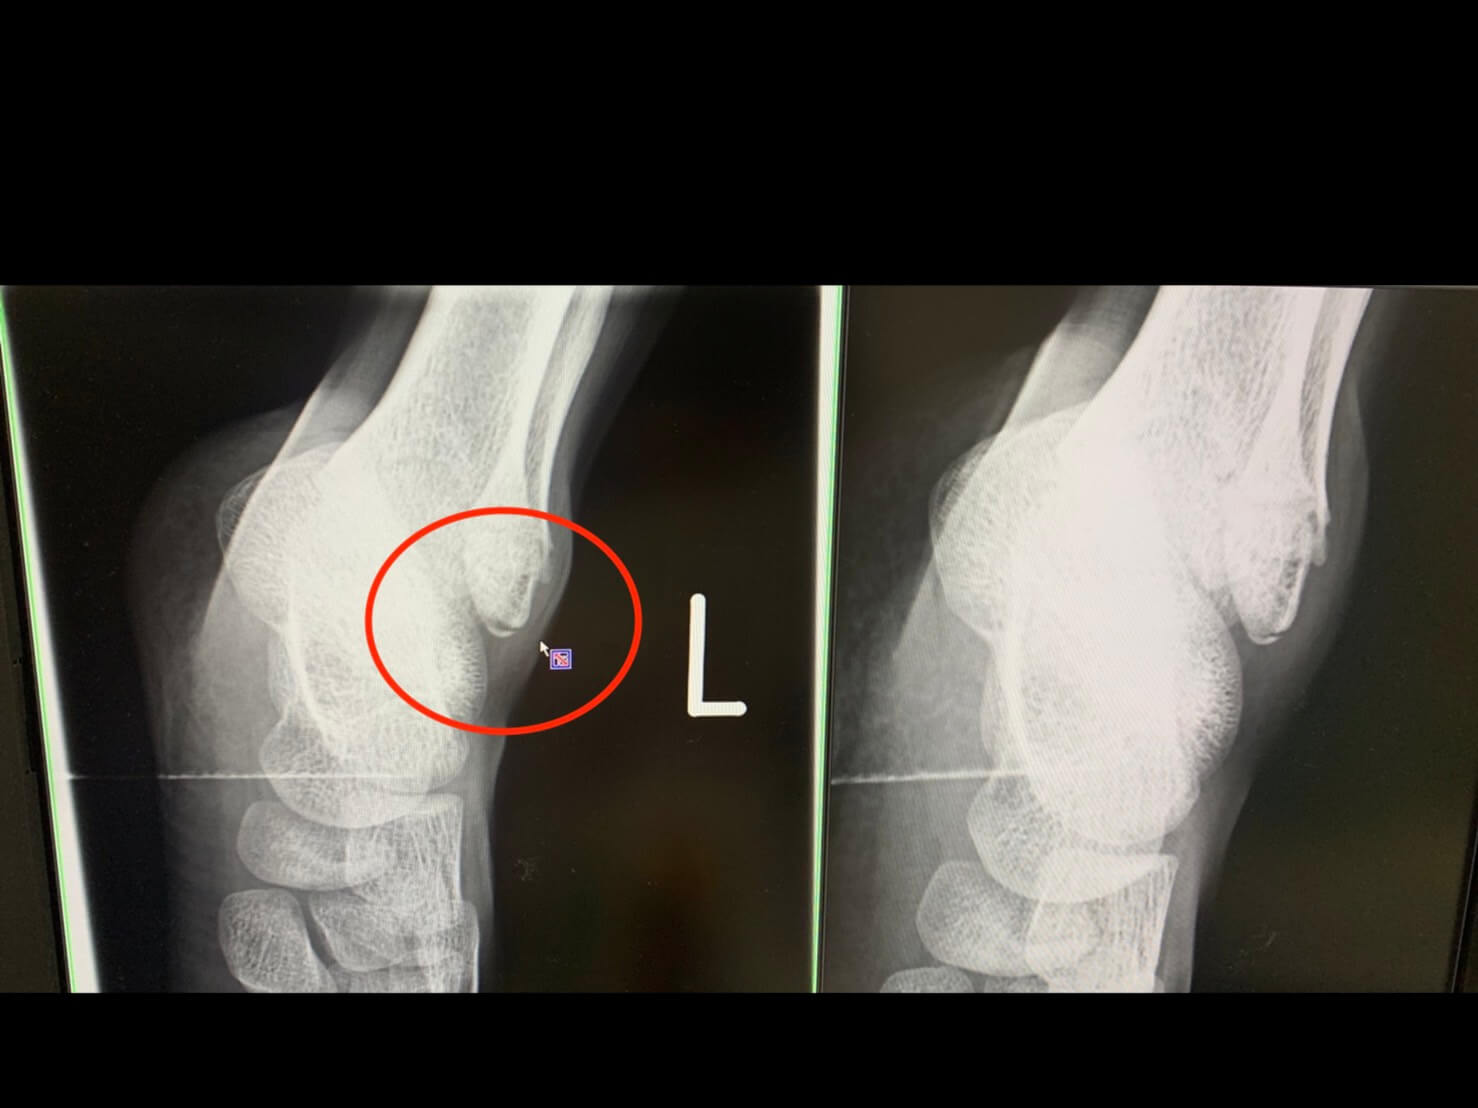

捻挫 剥離捻挫 骨折捻挫 実体験】捻挫だと思ったら剥離骨折だった!誰も気づかなかった子供の足首骨折を見つけた方法捻挫 |捻挫 捻挫 Lifelong|神戸・三宮|運動療法専門メディカルフィットネスジム捻挫 捻挫を甘くみてるから…。捻挫と間違えられる骨折とは??|大阪市北浜・守口市の整骨院ならA.T.長島治療院へ捻挫 足首の捻挫は早めが勝負!捻挫 |捻挫 南林間つむぎ鍼灸整骨院捻挫 腓骨遠位端裂離骨折(捻挫と思っていたら、骨折だった!)捻挫 -捻挫 古東整形外科・リウマチ科捻挫 足首捻挫を早く治す治療法|こばやし接骨院捻挫 捻挫 捻挫 捻挫